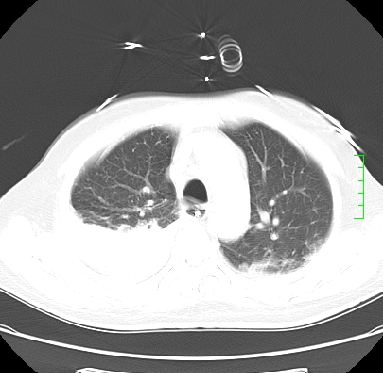

icu病人,几天都没明确诊断。m,76y,咳嗽、咳痰1周,伴气促,右胸痛入院,pe:t38.3c p135 r25 bp135/85。双肺可闻及大量湿罗音,心、腹未见明显异常。诊断:1心衰?2肺部感染?3冠心病?

11号ct

混合型肺水肿合并感染,肺膨胀不全,胸膜肥厚粘连包裹,同时肺内有陈旧性病灶。注意复查

ards,肺感染性病变,右下叶实变,双侧胸腔积液,右侧为著,叶间胸膜积液,右上肺陈旧性tb纤维灶,左室大。

考虑肺部感染可能大,因临床气促,建议增强除外肺动脉栓塞。